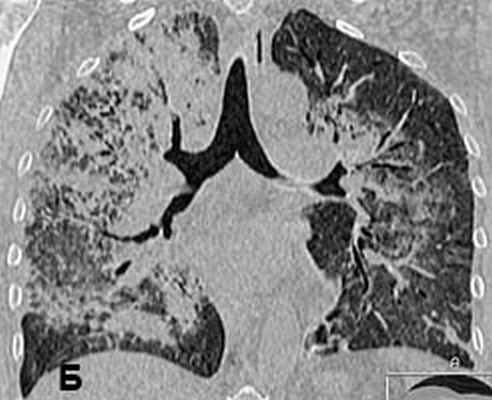

Рис 2. КТ органов грудной клетки от 11.01.2008. с реконструкцией: обширная диссеминация мелких «просовидных» теней на фоне диффузной очаговой пневмонии: инфильтрации со склонностью к слиянию; выраженные интерстициальные изменения.

У больной заподозрен микроскопический полиангиит. С целью морфологического подтверждения рабочего диагноза через двое суток после поступления в стационар была проведена краевая резекция легкого из миниторакотомного доступа. После этого начата пульс-терапия солумедролом 0.5 г/сутки в течение 4-х дней, однократно циклофосфан 800 мг/сут. в/в капельно. Своеобразная рентгенологическая картина легких в виде обширной диссеминации легких, просовидных теней на фоне диффузной очаговой инфильтрации со склонностью к слиянию и выраженных интрестициальных изменений, развившихся на фоне антибактериальной терапии требовала проведения дифференциальной диагностики между грибковым поражением легких (аспергиллез, криптококкоз), туберкулезом легких, синдромом Гудпасчера.